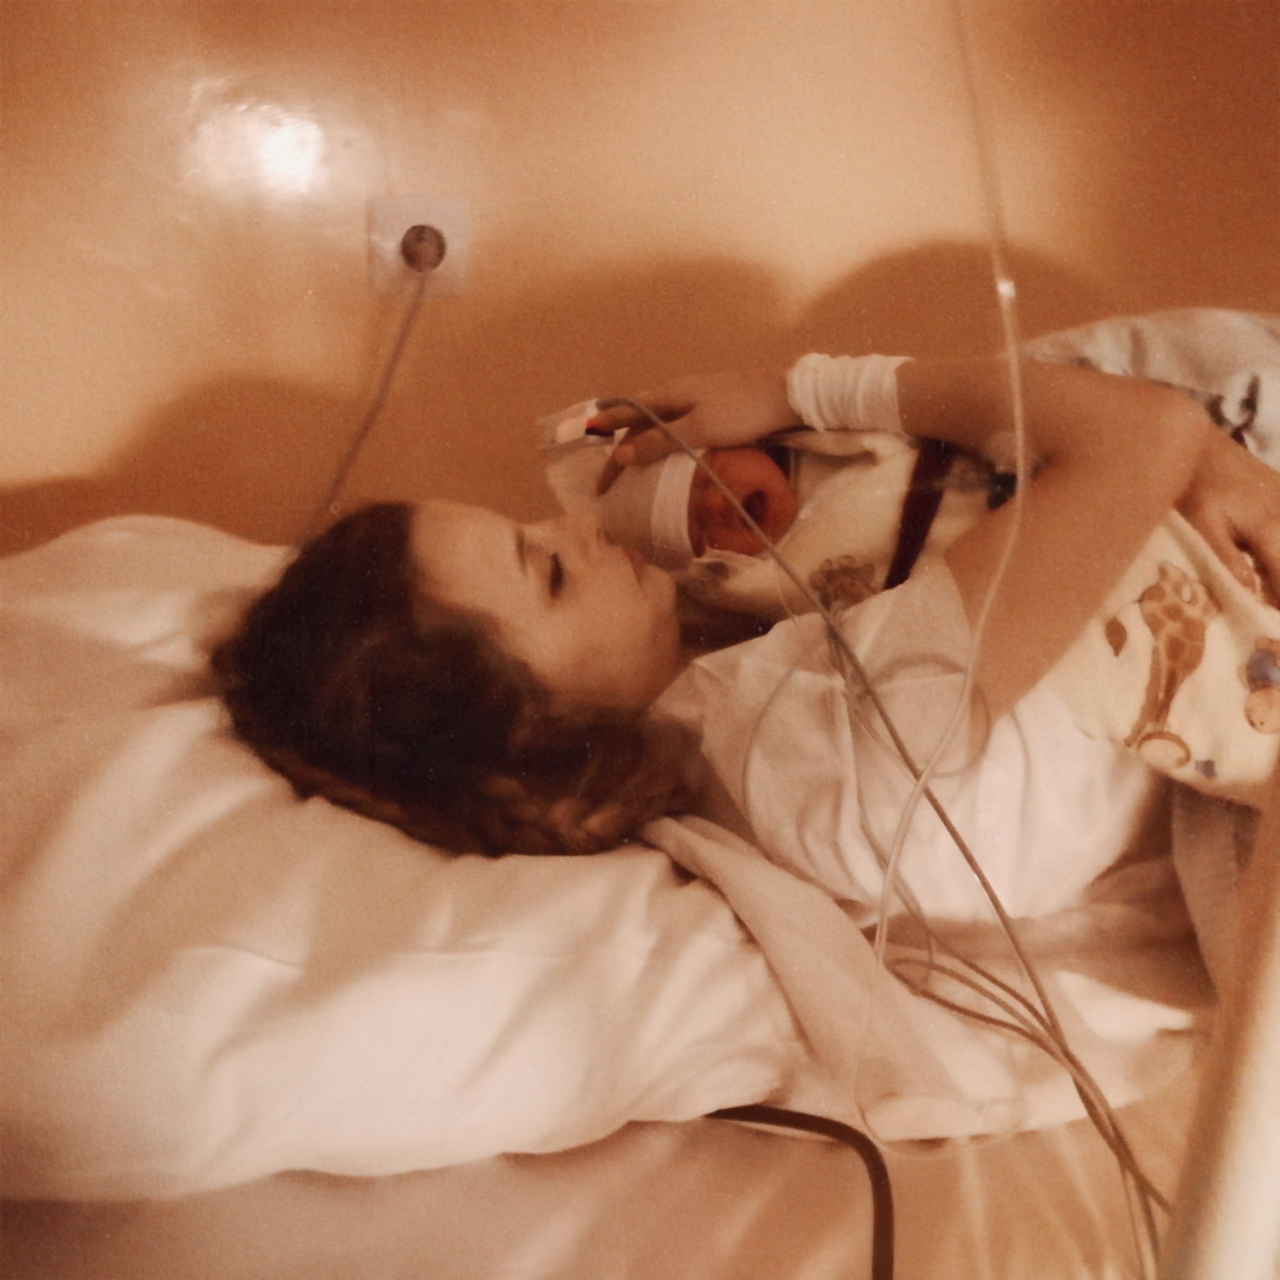

Zabrałam na porodówkę mleko modyfikowane. I stoję tu i teraz, z głową wysoko podniesioną, przed ławą przysięgłych, nie wstydząc się „zbrodni” której dokonałam.

Oszczędziłam sobie strachu, już wystarczyło mi że wszystko u tego człowieka było małe i trzeba było być nadwyraz ostrożnym. Główka, rączki, brzuszek. Przewijanie, ubieranie. Wszystko do wykonania, jednak przy akopaniamencie płaczu dosyć utrudnione. No i karmienie, chyba najważniejsze. Podstawowa potrzeba, którą ja chciałam spełnić za wszelką cenę, chciałam by dziecię nie było głodne, ile wykarmię tyle wykarmię, a jak będziesz chciała jeszcze to Ci dam resztę. Po kryjomu. Pewnie położne nie robiłyby problemu, ale ja nie chciałam się spowiadać, czy mi się udało karmić tą piersią, czy próbowałam, czy wiem jak nastawić dziecko, czy może spróbuję jeszcze raz. Spoglądać na nie błagalnym wzrokiem, czy wezmą ją i nakarmią, bo chyba serio jest głodna, płacze. Trudny był dla mnie ten płacz, trudne było dla mnie oczekiwanie na litość.

I nawet nie wiesz, jak dobrze wspominam ten drugi pobyt, całkowicie na moich warunkach.